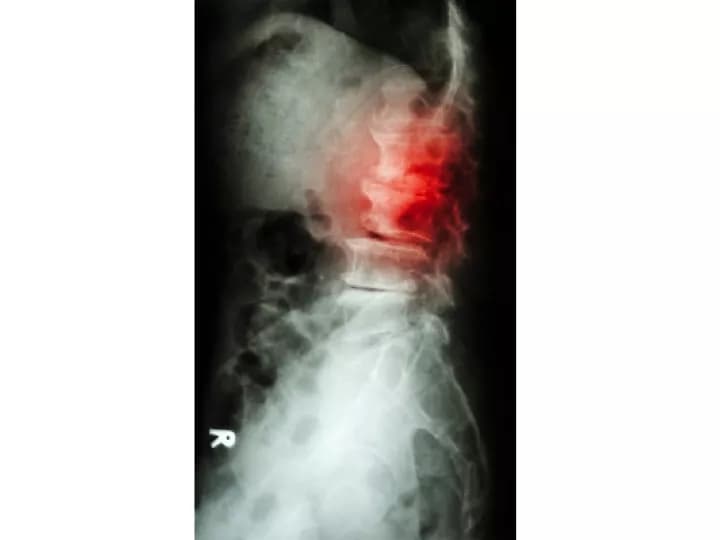

• X-rays: X-rays are useful in showing if the lumbar bone has slipped forward and the extent of the slippage. This diagnostic test may also show if any abnormalities due to advancing age are present within the spine, such as the formation of bone spurs